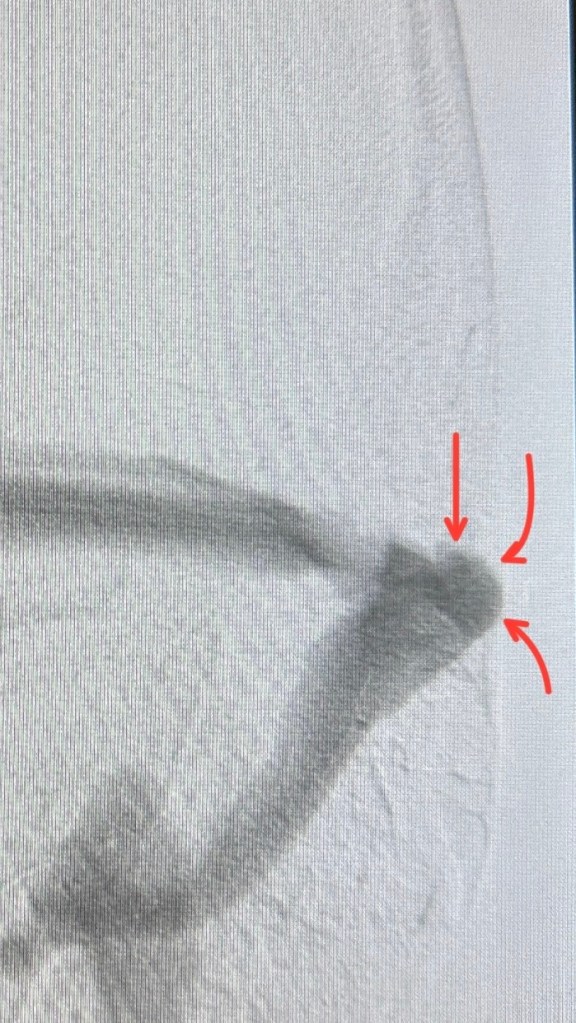

المريض كان بيعاني من طنين نابض مستمر. الأشعة بيّنت وجود اتساع واضح في أحد أوردة المخ ملاصق لمنطقة حساسة قريبة من الأذن.

الصور التوضيحية

– السهم الأحمر 🔴 بيشير للجزء المتسع قبل العلاج.

– اللون الأصفر 🟡 بعد تركيب الدعامة، موضح إن التمدد اختفى تماماً وأن الوريد رجع لحجمه الطبيعي.